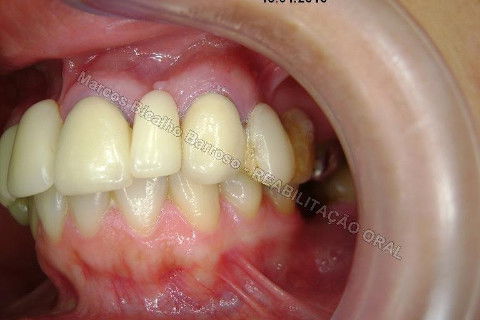

Paciente sexo feminino, 40 anos, queixava-se da situação da PPR superior, sem estabilidade, fraturas constantes nos dentes instalados. Sua vontade era resolver somente o problema da arcada superior, por questões financeiras. Logo no exame clínico inicial verifiquei a necessidade da reabiltiação inferior, pois este caso consistia em desarmonia oclusal severa, principalmente pela extrusão dos elementos 13,14 e 15 devido ausência de várias unidades inferiores. A proposta aceita pela paciente foi a instalação de 5 implantes na mandíbula + 5 implantes na maxila + tratamento endodôntico, osteoplastia e gengivoplastia nos dentes extruídos, incluindo núcleos metálicos e coroas em metalocerâmica (13,14,15). As coroas sobre implantes serão incialmente provisórias em resina fotopolimerizável e posteriormente metalocerâmica, de acordo com as possibilidades da paciente. Os procedimentos nos elementos extruídos serão apresentados em momento oportuno.